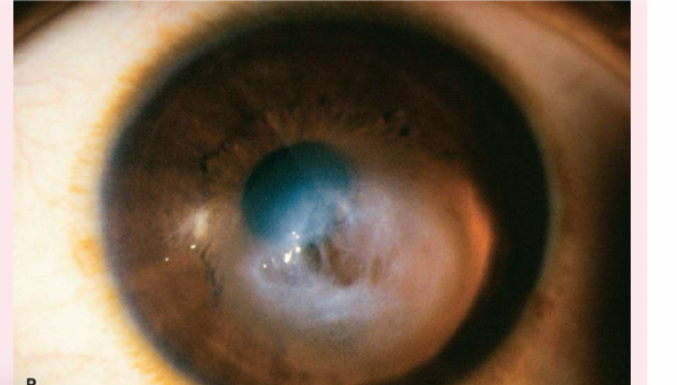

corneal scar

which appears grayish white, may be due to inflammation or an old injury.

Nuclear cataracts

appear gray when seen with a flashlight; they appear as a black spot against the red reflex

Peripheral cataracts

look like gray spokes that point inward when seen with a flashlight; they look like black spokes that point inward against the red reflex when seen through an ophthalmoscope.